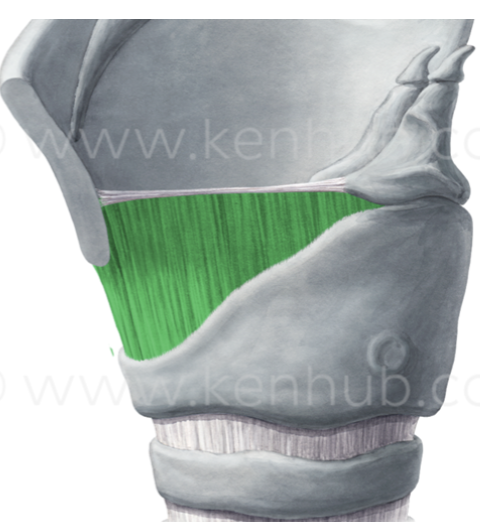

What is this muscle?

Cricothyroid (rocks thyroid forward, pitch up)